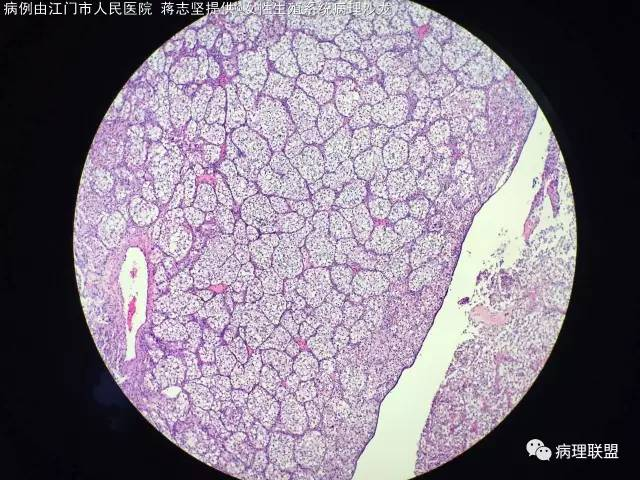

女,20岁,宫腔赘生物,子宫下段后壁2×1×1cm,HCG 不高,一年前卵巢手术,病理,浆液性囊性腺纤维瘤,本次宫腔镜手术(病例由江门市人民医院 蒋志坚提供,致谢!)